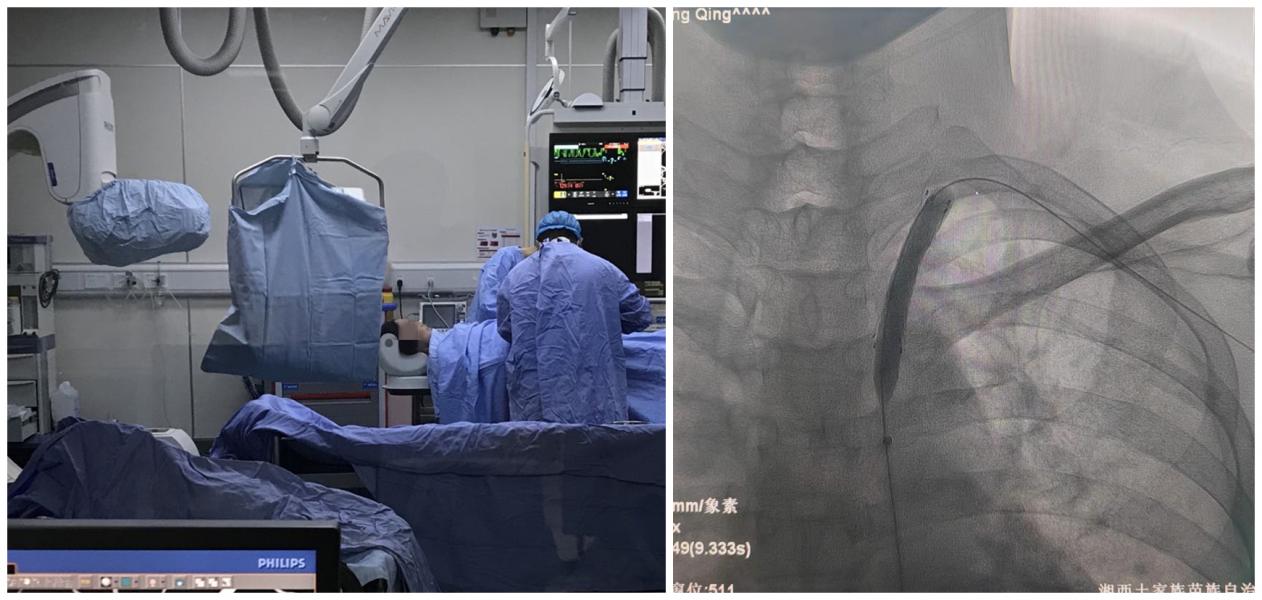

在介入科的密切配合下,神经外二科团队在局麻下为黄先生实施左侧锁骨下动脉近端狭窄支架成形术,术中支架与血管壁贴合良好,对位准确无移位,左侧椎动脉血流正向,手术顺利完成。

手术中操作情况